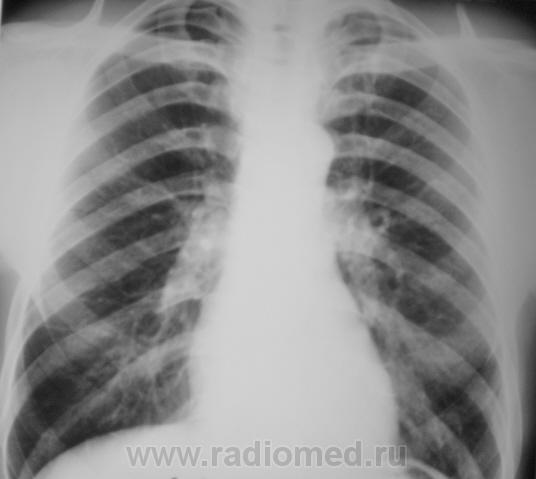

Фактически, эти три случая, часть эксперимента (все не представлено, да и не нужно), который был проведен фтизиатрами и рентгенологами с полным соблюдением стандарта.

Очень часто на пленочной рентгенограмме, и это общеизвестно, мы, в основном, видим «плотненькое» и «обызвествленное». Не можем мы видеть на рентгенограмме «мягкое», а иногда и средней интенсивности, скрытое за костными компонентами грудной клетки. Сравнивая «пленочную рентгенограмму» с цифровой рентгенограммой фиксируется значительная разница теневой картины.

Вот, мы и провели эксперимент, а именно обзорная на пленке, а томограмма – на «цифре».

Какие мнения будут уважаемые коллеги? Не все можно объяснить «цифровым фотошопом» и отсутствием «экранной нерезкости» на цифровых снимках…